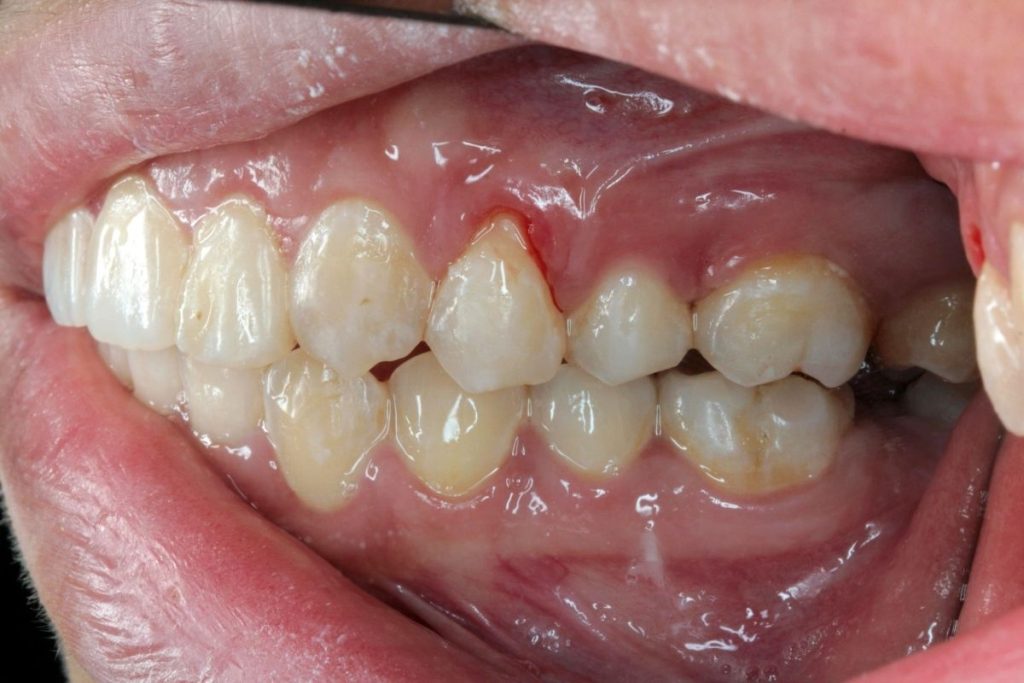

Diş eti kanaması, ağız hijyeninin bozulduğu durumlarda en sık görülen ağız sağlığı şikayetlerinden biridir. Diş etlerinde minik kanamalar, özellikle fırçalama veya diş ipi sırasında açığa çıkar. Bu durum sıklıkla hafife alınsa da, altında yatan etkenler gingivitisten ciddi periodontal hastalığa kadar ilerleyebilir.

Diş eti kanaması, diş etlerinin yüzeyindeki ince ve hassas dokuların kanamasıdır. Genellikle diş fırçası, diş ipi veya zorlanma sırasında ortaya çıkabilir. Çoğunlukla plak ve diş taşı birikimi gibi lokal nedenlerle ilişkilidir. Ancak bazen sistemik etkenler, vitamin eksiklikleri veya hormonal değişimler de kanamalara neden olabilir.

Kanama, diş eti sağlığının bozulduğuna dair erken bir uyarı sinyalidir ve göz ardı edilmemelidir. Zamanında müdahale edilmezse, diş eti iltihabı daha ileri seviyelere ilerleyebilir.

- Diş eti hattında kızarıklık ve şişlik